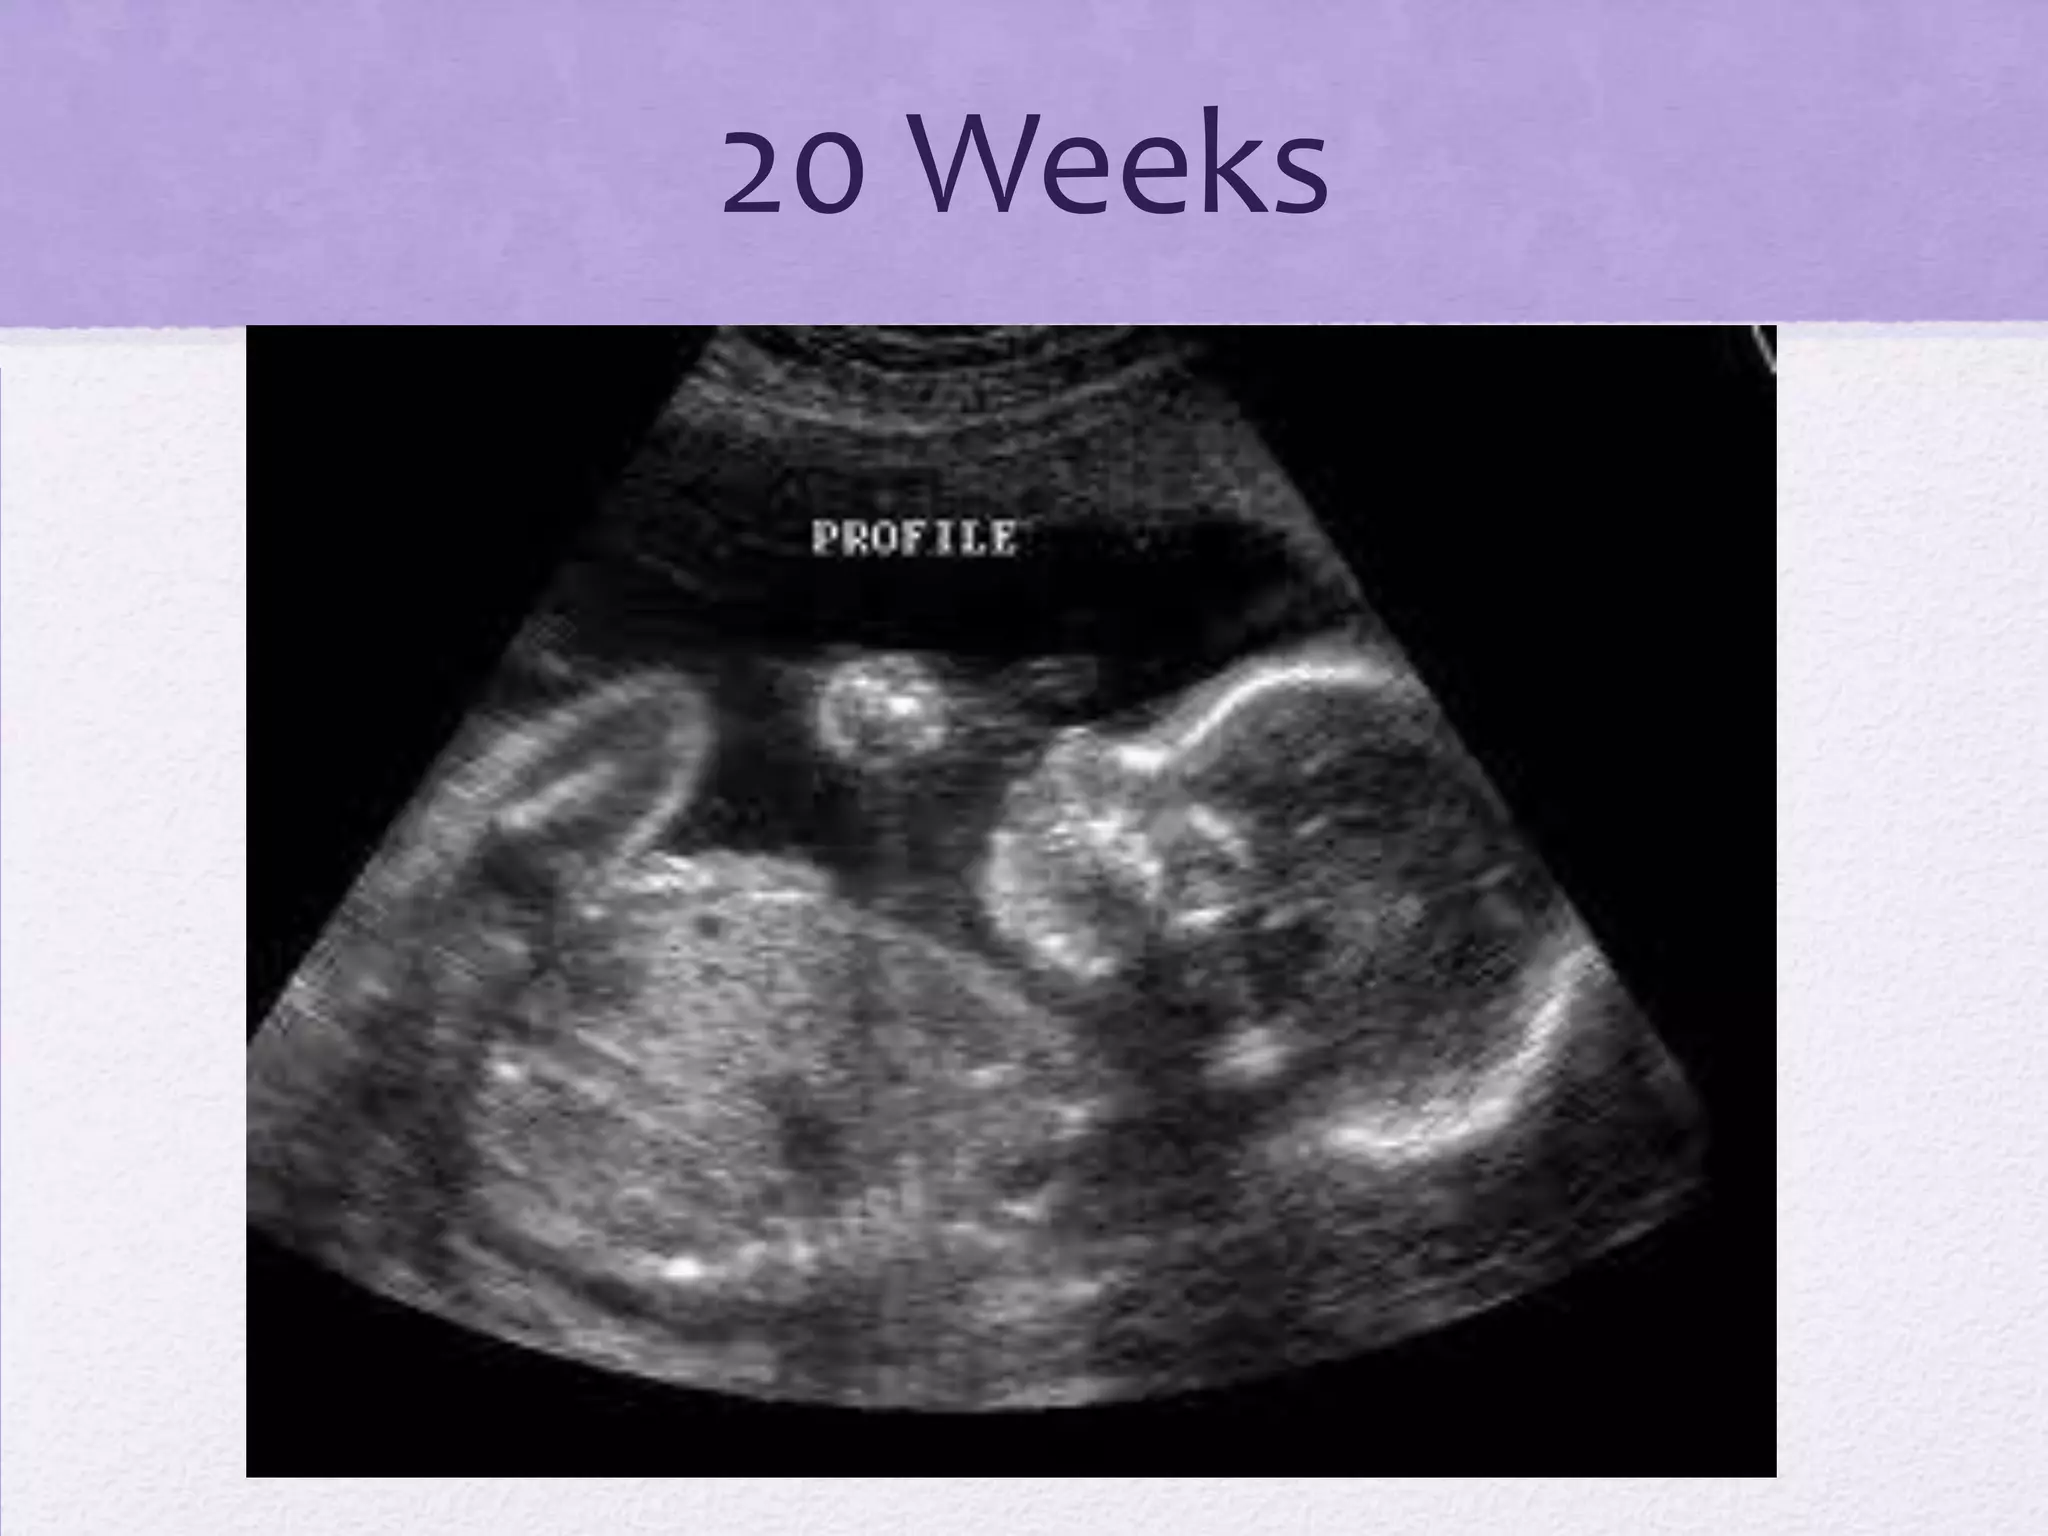

The document outlines the stages of labor and delivery from conception through birth including fetal development timelines, stages of labor, delivery options, birthing places, pain management options, and the possibility of determining fetal sex and viewing the baby through ultrasound technology. Key stages of development include a brain forming at 24 days, a heart beating at 6 weeks, and viability outside the womb reaching 24 weeks. Vaginal delivery, assisted delivery through forceps or vacuum, and cesarean section are covered as options.